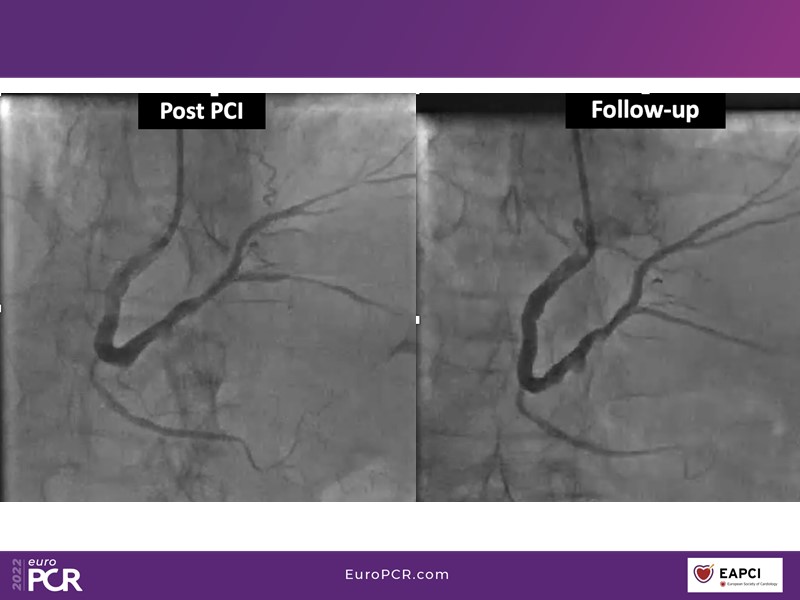

- To find out more about the application and mechanism of a sirolimus coated balloon for coronary artery disease treatment with case presentations in complex settings

- To understand how useful is a DES and DCB stent platform in complex coronary artery disease settings with case demonstrations and follow-up in diabetes mellitus